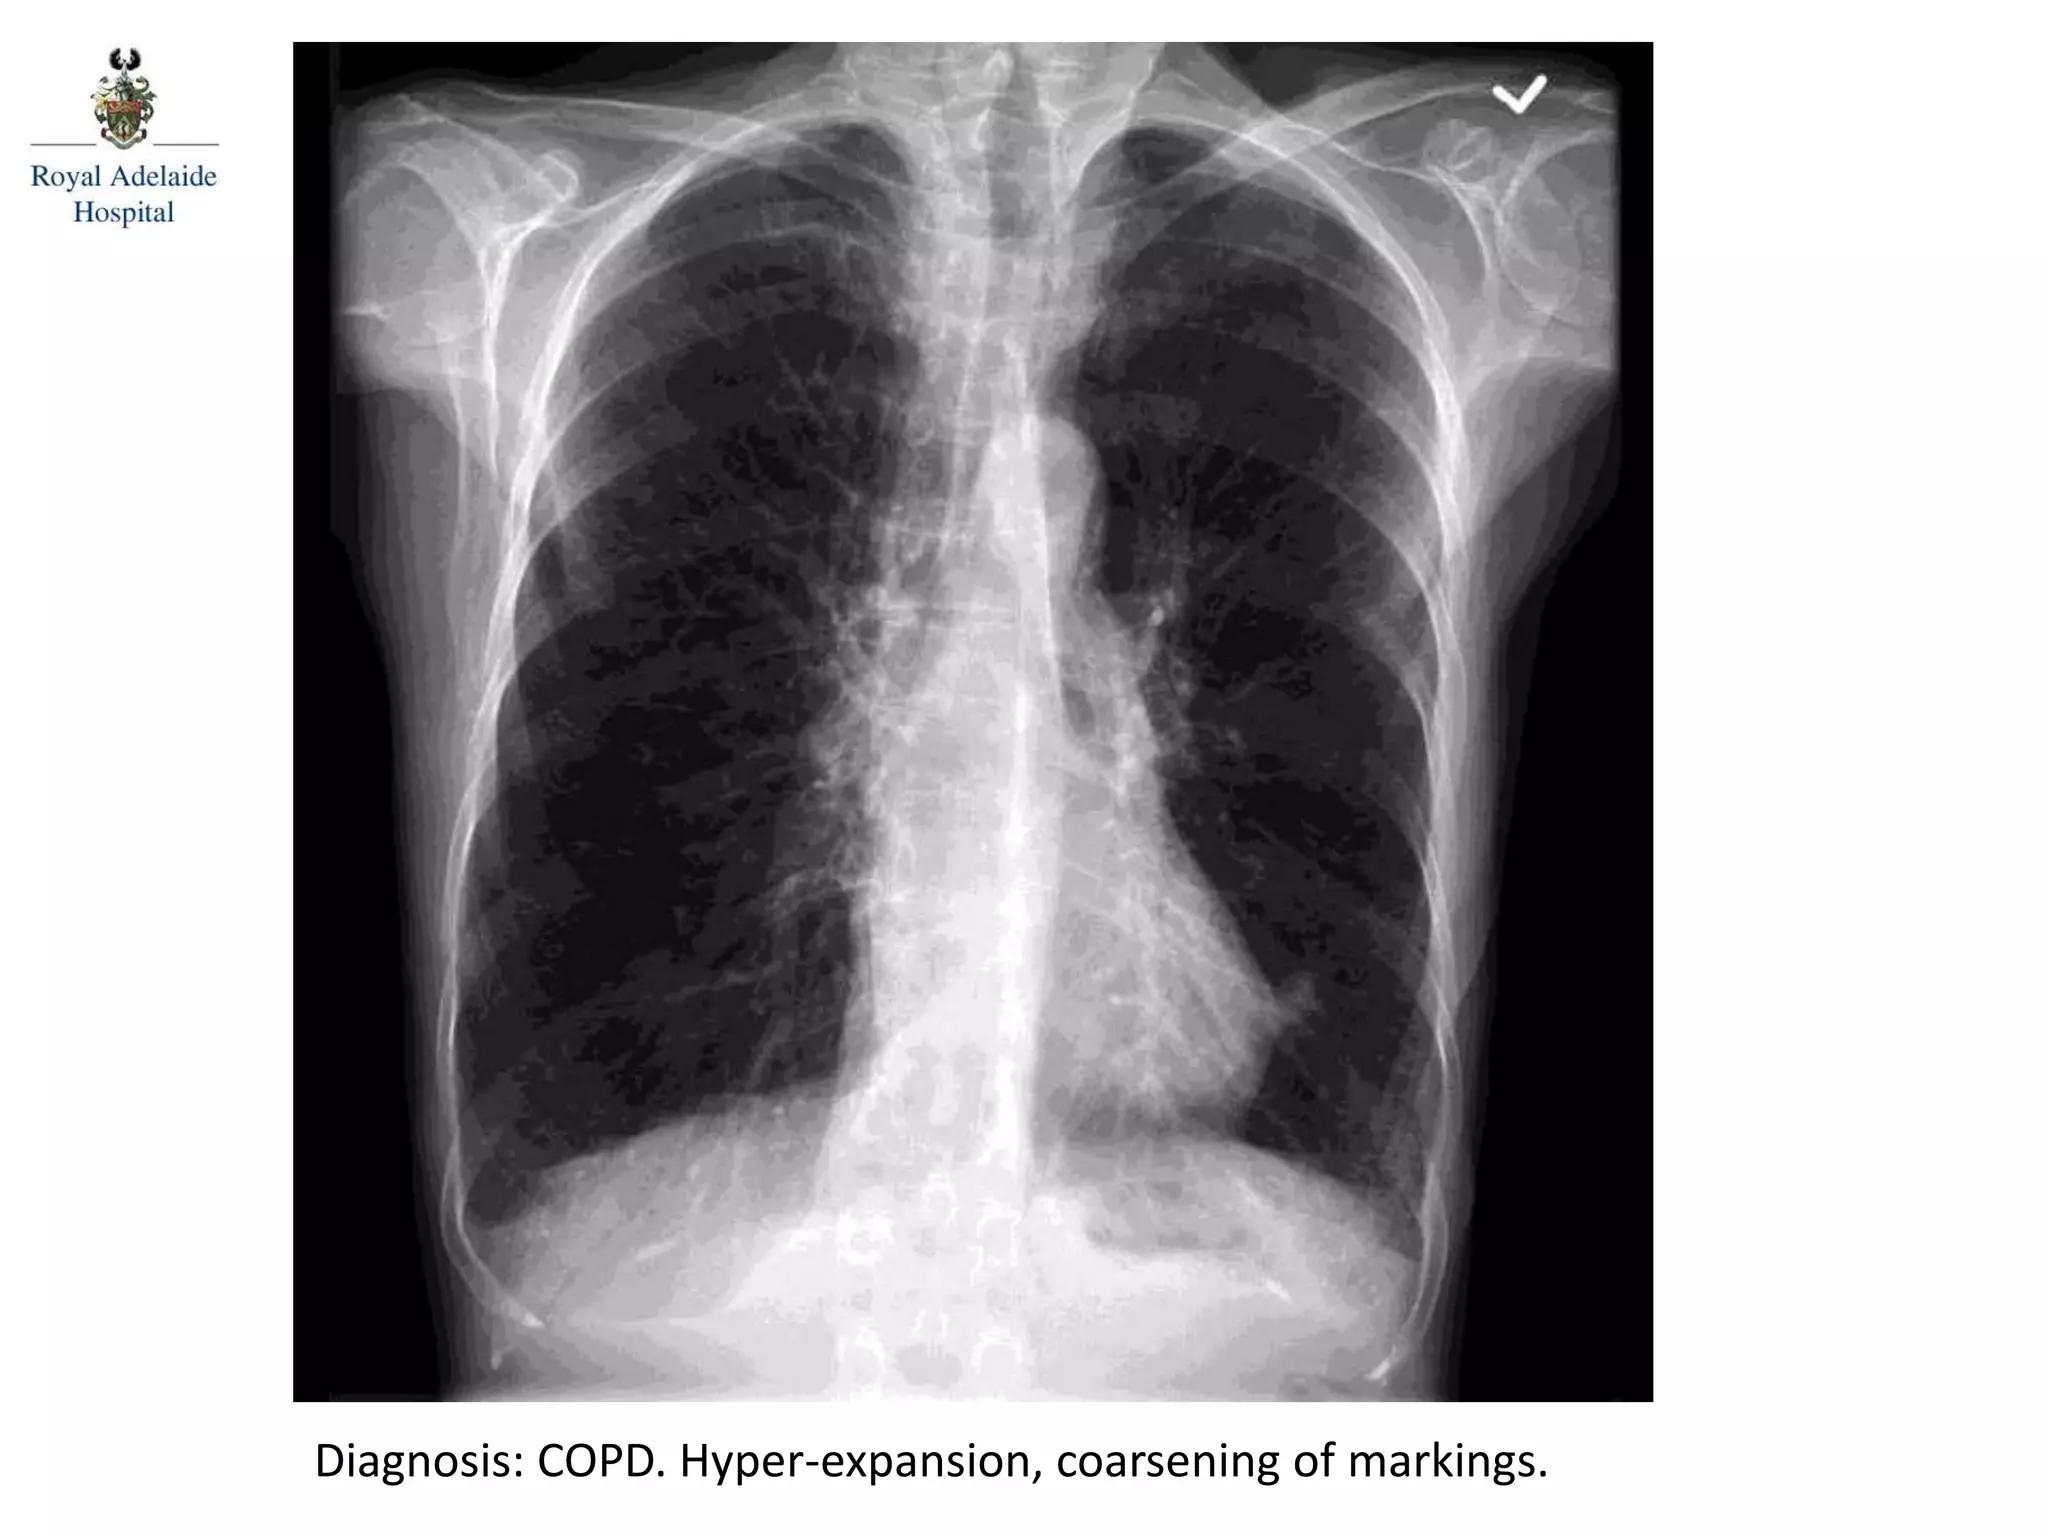

Diagnosis: COPD. Hyper-expansion, coarsening of markings.